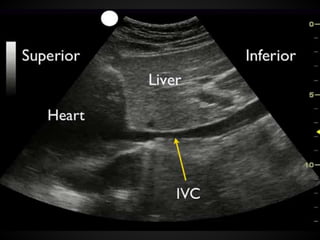

Flat IVC: IVC collapses >50% during the

respiratory cycle

The Significance of the IVC

in Volume Status

The overall size of the vessel is not as

important as the variability.

Increasing the intra-thoracic pressure

would result on an increased IVC size but

might not change the variability. A small

IVC on a hypotensive ventilated patient is

diagnostic of hypovolemia, but a full IVC

does not rule out this diagnosis.

Volume Status Diagnostic ofhypovolemia in hypotensive patients: empty heart or flat IVC In hypovolemia, the ventricular walls will come together or ‘‘kiss,’’ or in cardiologist lingo, an ejection fraction >70% Flat IVC: IVC collapses >50% during the respiratory cycle

The Significance ofthe IVC in Volume Status The overall size of the vessel is not as important as the variability. Increasing the intra-thoracic pressure would result on an increased IVC size but might not change the variability. A small IVC on a hypotensive ventilated patient is diagnostic of hypovolemia, but a full IVC does not rule out this diagnosis.